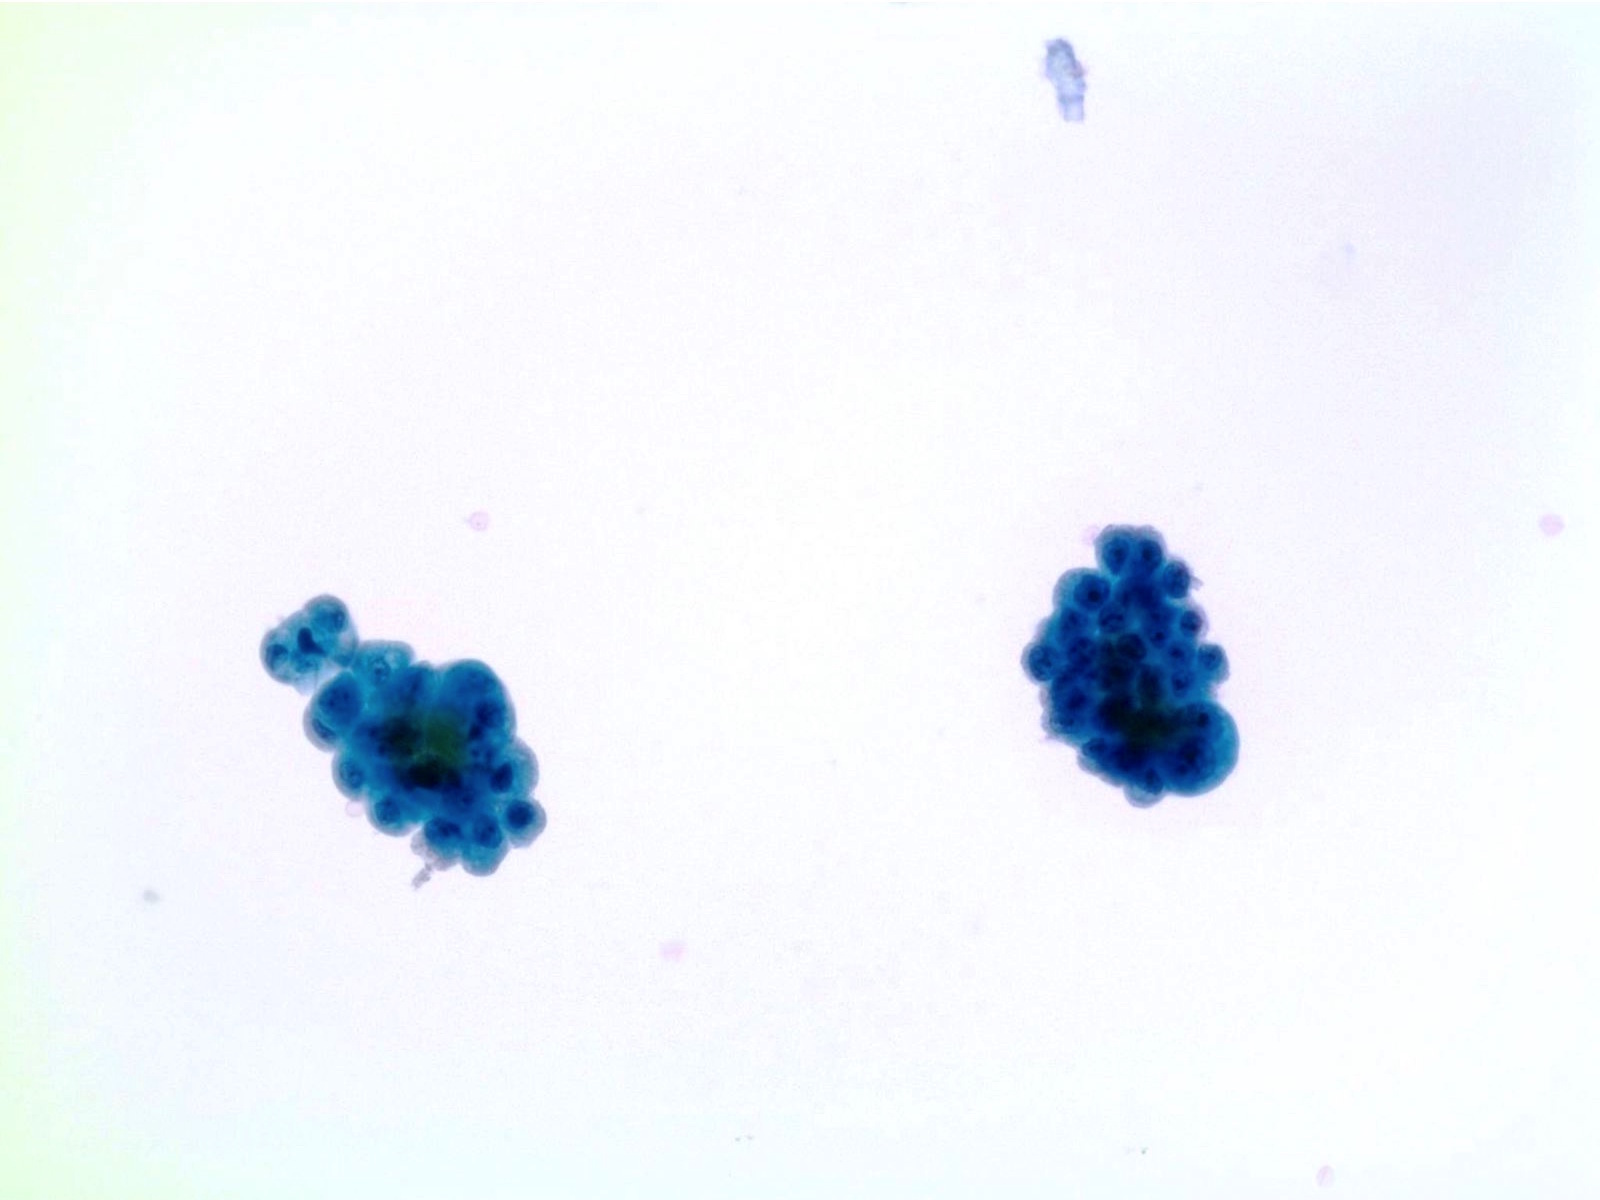

Low Grade Urothelial Neoplasia (LGUN)

- LGUN is a combined cytologic term for low grade papillary urothelial neoplasms, which includes urothelial papilloma, papillary urothelial neoplasm of uncertain malignant potential (PUNLMP) and low grade papillary urothelial carcinoma (LGPUC)

- Definitive diagnosis of LGUN is possible only in the presence of this cytologic criteria (regardless of voided urine or instrumented urine):

- 3 dimensional cellular papillary clusters with fibrovascular cores including capillaries

- Cellular papillary clusters are defined as clusters of cells with nuclear overlapping forming papillae

- The following cytologic features should be categorized as NHGUC:

- 3 dimensional cellular clusters without fibrovascular cores

- Increased numbers of single monotonous (non umbrella) cells

- Cytoplasmic homogeneity

- Nuclear border irregularity

- Increased N/C ratio

- A comment may be added to suggest LGUN in these cases without definitive cytomorphologic features

- Rate of progression is 0% for papillomas, 3.6% for PUNLMP and 5 - 25% for LGPUC (WHO / ISUP classification (2004))